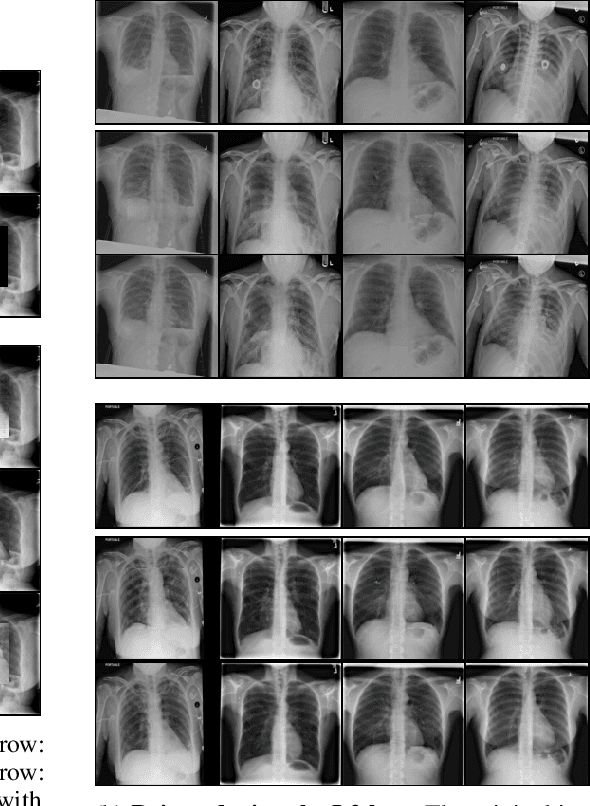

Abstract:Chest X-rays are one of the most commonly used technologies for medical diagnosis. Many deep learning models have been proposed to improve and automate the abnormality detection task on this type of data. In this paper, we propose a different approach based on image inpainting under adversarial training first introduced by Goodfellow et al. We configure the context encoder model for this task and train it over 1.1M 128x128 images from healthy X-rays. The goal of our model is to reconstruct the missing central 64x64 patch. Once the model has learned how to inpaint healthy tissue, we test its performance on images with and without abnormalities. We discuss and motivate our results considering PSNR, MSE and SSIM scores as evaluation metrics. In addition, we conduct a 2AFC observer study showing that in half of the times an expert is unable to distinguish real images from the ones reconstructed using our model. By computing and visualizing the pixel-wise difference between source and reconstructed images, we can highlight abnormalities to simplify further detection and classification tasks.

Abstract:Generative adversarial networks have been successfully applied to inpainting in natural images. However, the current state-of-the-art models have not yet been widely adopted in the medical imaging domain. In this paper, we investigate the performance of three recently published deep learning based inpainting models: context encoders, semantic image inpainting, and the contextual attention model, applied to chest x-rays, as the chest exam is the most commonly performed radiological procedure. We train these generative models on 1.2M 128 $\times$ 128 patches from 60K healthy x-rays, and learn to predict the center 64 $\times$ 64 region in each patch. We test the models on both the healthy and abnormal radiographs. We evaluate the results by visual inspection and comparing the PSNR scores. The outputs of the models are in most cases highly realistic. We show that the methods have potential to enhance and detect abnormalities. In addition, we perform a 2AFC observer study and show that an experienced human observer performs poorly in detecting inpainted regions, particularly those generated by the contextual attention model.